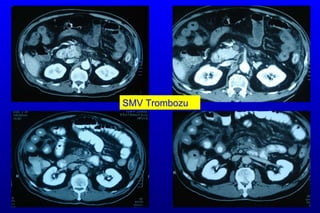

T.A.  55/K Şikayet:  K arın ağrısı Hikaye: 3 gündür devam eden karın  a ğrısı  Ek hastalık:   HT ve atrial fibrilasyon  Kullandığı ilaçlar :  Tarka 180 mg tb 1x1 Coumadin tb 1x1 FM:  TA:130/70 Nb:84,   sol alt kadranda hassasiyet (+) defans (-) rebound(-) barsak sesleri dört kadranda normoaktif  Lab: Lök:15600   Hb:8,6 Hct:29,7 PLT:367000 BK:Normal l a ktat :2,8  Batın BT anjio:  SMA distalinde parsiyel trombüs ve ince barsak tipi hava sıvı seviyeleri

KLİNİK 15/03/2009 :Hasta acil cerrahi kliniğine kabul edildi. Yapılan tetkiklerinde SMA distalinde parsiyel trombüs saptanması üzerine diagnostik laparoskopi yapıldı. Low flow state saptandı. Ameliyat sonrası anjiografi yapılarak tPA  uygulandı. İşlem sonrası yoğun bakıma alınan hastanın sorunu olmadı. 16/03/2009 :Hastaya kontrol anjiografi yapıldı parsiyel trombüs görüntüsü devam ediyor. Hastaya tedavi dozunda DMAH başlandı.

KLİNİK 15/03/2009 :Hastaacil cerrahi kliniğine kabul edildi. Yapılan tetkiklerinde SMA distalinde parsiyel trombüs saptanması üzerine diagnostik laparoskopi yapıldı. Low flow state saptandı. Ameliyat sonrası anjiografi yapılarak tPA uygulandı. İşlem sonrası yoğun bakıma alınan hastanın sorunu olmadı. 16/03/2009 :Hastaya kontrol anjiografi yapıldı parsiyel trombüs görüntüsü devam ediyor. Hastaya tedavi dozunda DMAH başlandı.